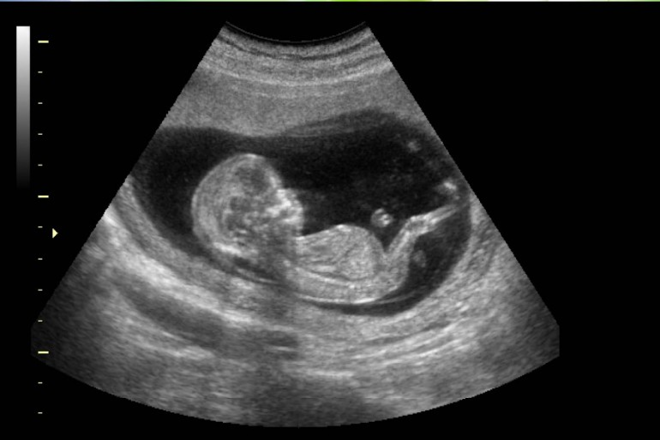

¿Se asocia la ecografía prenatal con los trastornos del espectro autista (TEA)?

16 febrero 2018

Los hallazgos de este estudio son en general consistentes con datos previos que sugieren que la ecografía prenatal no es un factor causal suficiente de los TEA. Sin embargo, no se descarta su potencial como un factor de estrés ambiental en un sistema genéticamente vulnerable. JAMA Pediatrics, 12 de febrero de 2018